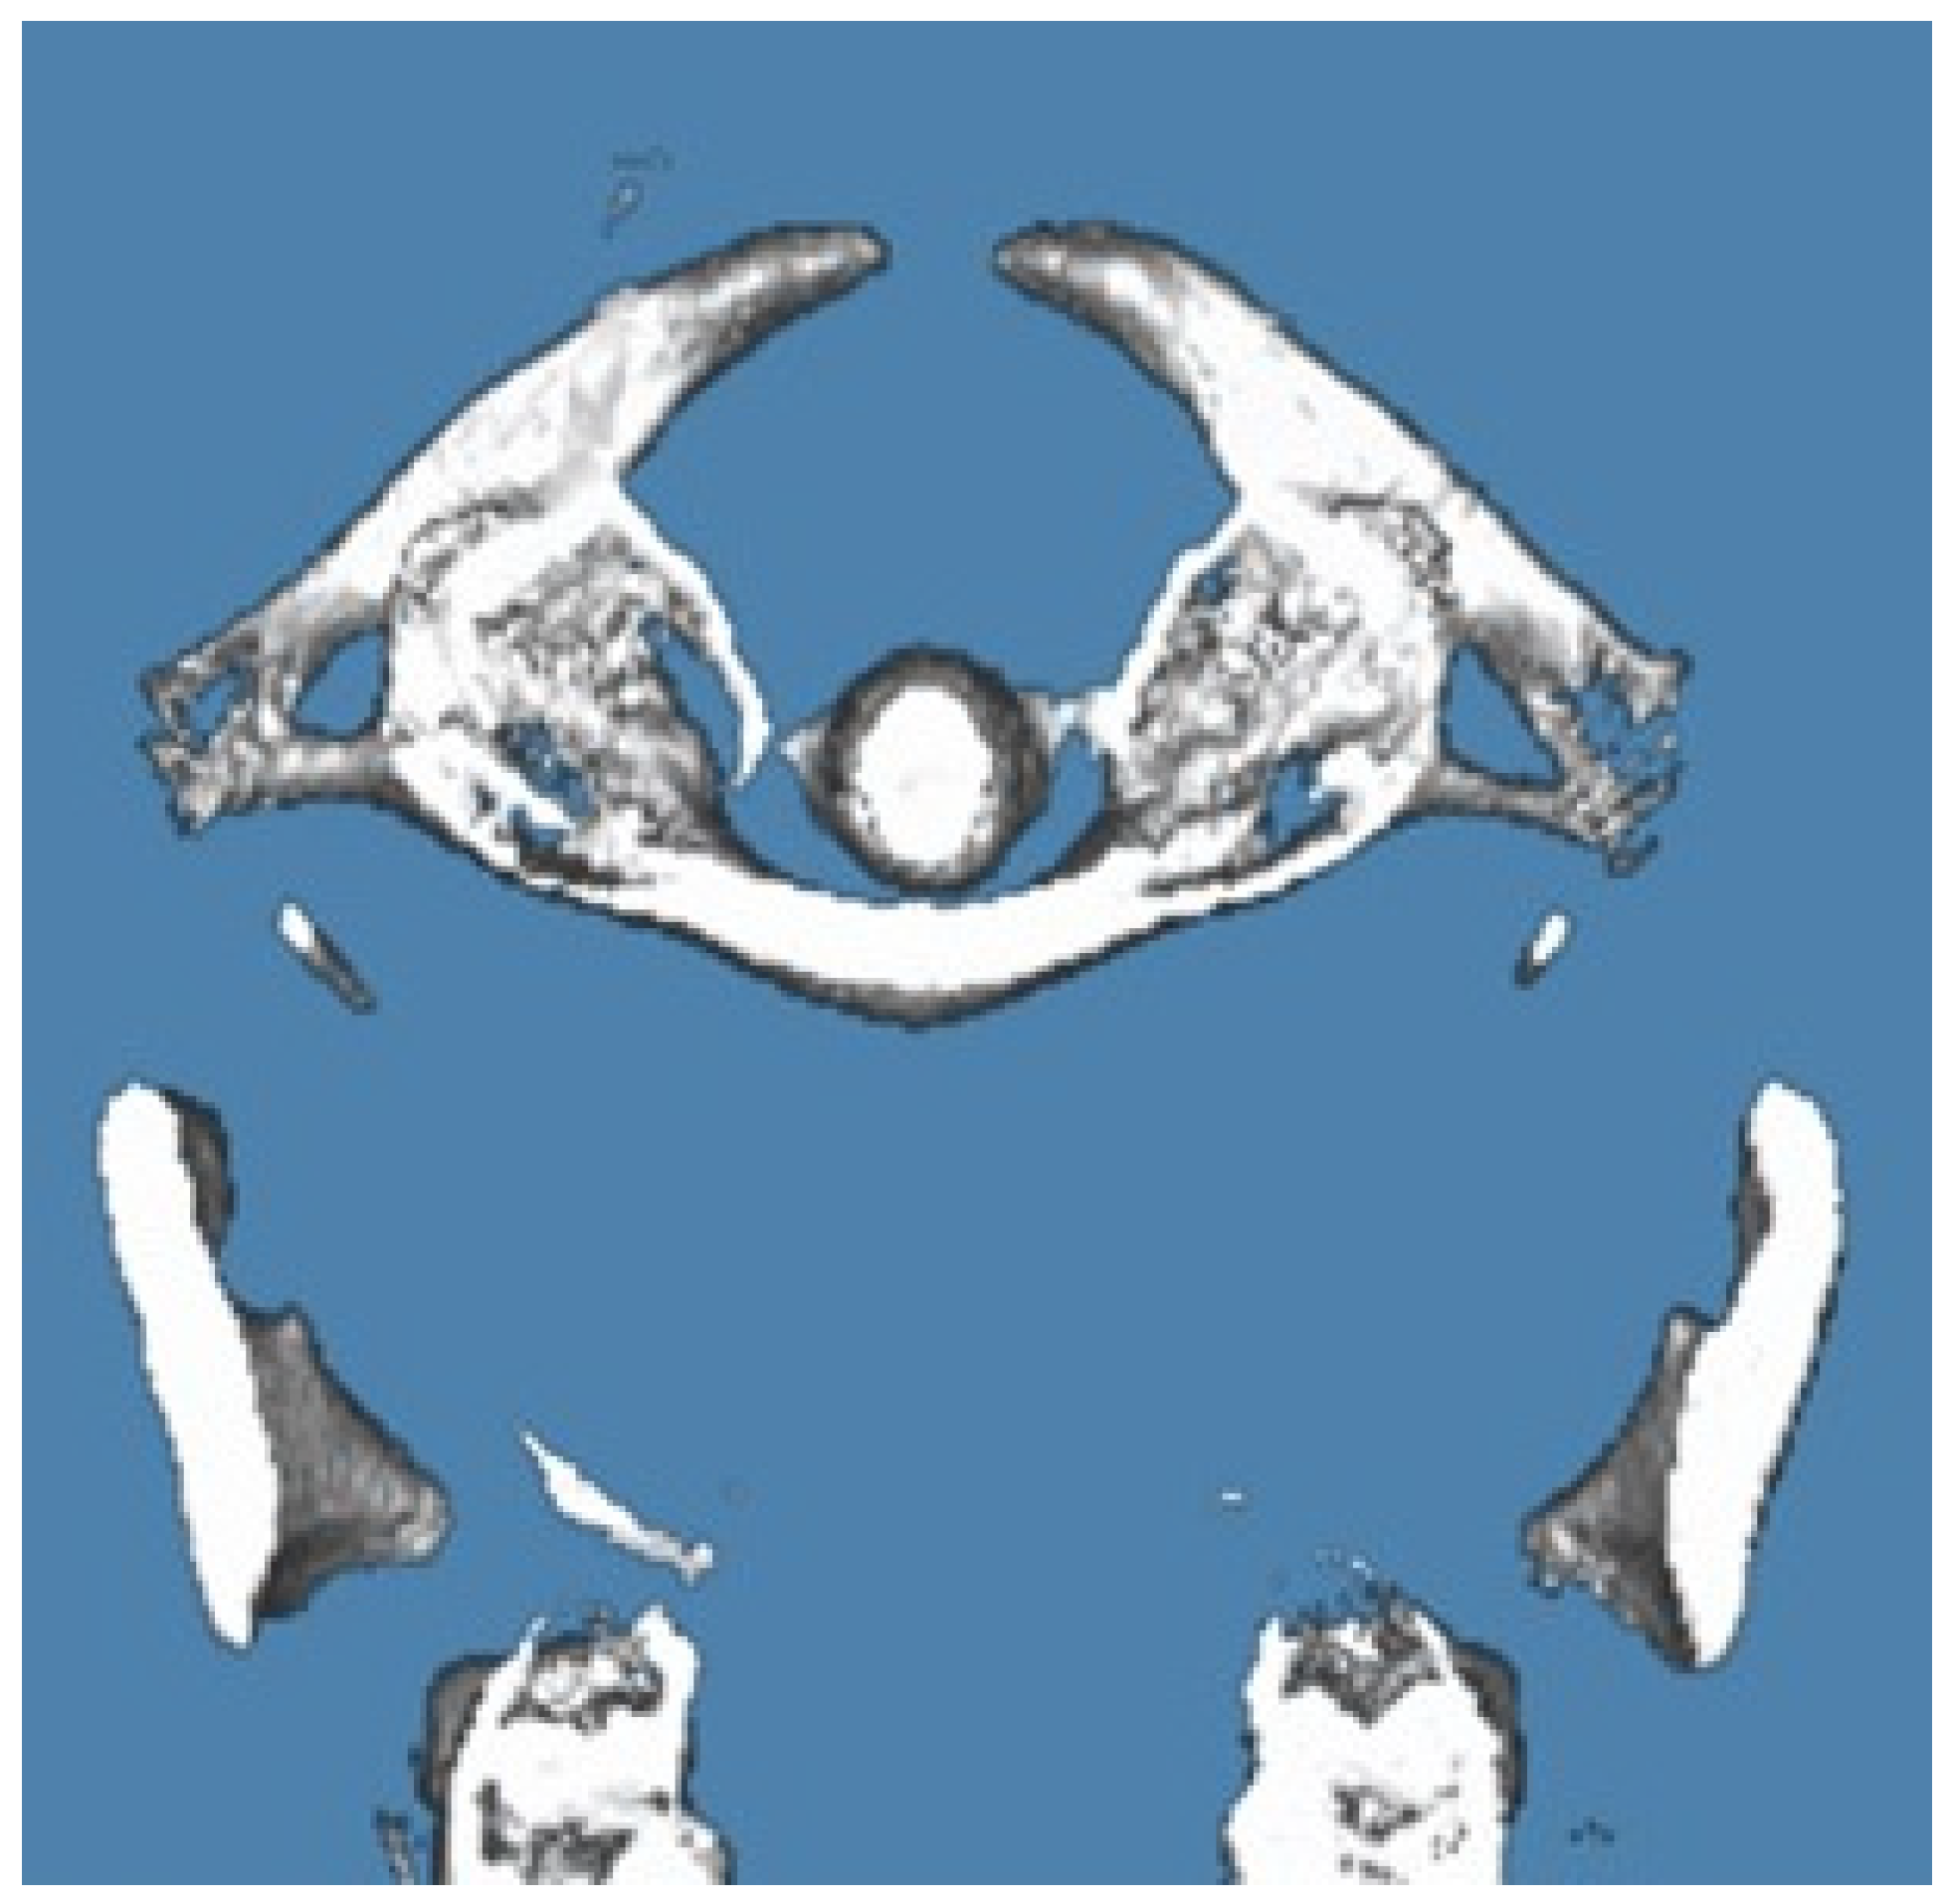

3.2.1. Case Report 1: Bilateral Complete Ponticulus Posticus and Complete Atlantal Posterior Arch Defect Type A in a 17-Year-Old Female: Clinical and Imaging Findings

| 1 | 17 years | Complete APAD | Bilateral Complete | Occasional mild neck stiffness; no significant neurological symptoms | Routine monitoring; no immediate intervention required | Remained symptom-free; routine imaging for follow-up |